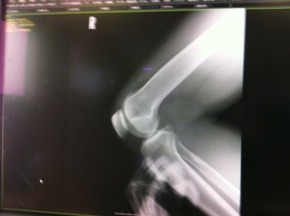

それにしても人間って本当に精巧に出来ていてこんなレントゲン写真を見ていても「神様」の存在が頭に浮びますね。

現在はその構造をメスを入れる訳でもなくはっきりと見る事が出来ます!

以前にも紹介した3DCTがそうなんですがこの画像、実は今も怪我で苦労をしている右膝そのものなんです!

お皿が3つに割れたのも欠けた骨が中にあるのもしっかりと写っています!

こうなると先生の言う事もしっかりと理解するしか方法がありませんが凄い時代になった物です!!